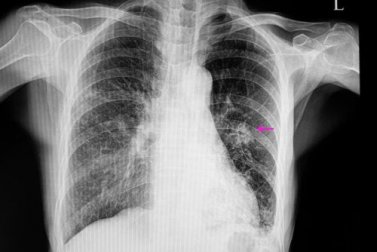

Nestes casos, o nódulo geralmente apresenta uma aparência irregular na radiografia, com bordas mal definidas. Seu tamanho geralmente também é menor que os benignos e, além disso, está associado a certos fatores de risco, como:

Feito isso, é necessário realizar determinados testes de imagem para localizar o nódulo. Além disso, as imagens nos permitem observar certas características, como forma e tamanho, que são importantes para diferenciar um benigno de um possivelmente maligno.

Os mais utilizados são radiografia de tórax e tomografia computadorizada. Para saber exatamente a causa do nódulo pulmonar, algumas vezes são realizadas biópsias que permitem a análise do tecido que o forma.